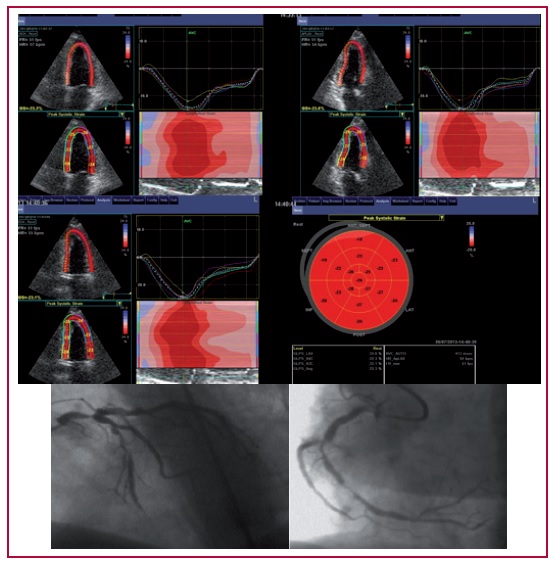

Introducción: El eco estrés evidencia la isquemia miocárdica como un trastorno regional y transitorio de la motilidad. El análisis visual es subjetivo y depende de la experiencia del operador, lo que ha motivado la búsqueda de un método semiautomático que permita minimizar esta limitación y así mejorar la confiabilidad y reproducibilidad de la prueba. Esto ha generado creciente interés en la introducción de la medición del strain longitudinal bidimensional antes del eco estrés y durante y después de él. Su determinación en las diferentes fases de apremio, en caso de que sea útil, permitiría reducir otras limitaciones, como la imposibilidad de alcanzar la frecuencia cardíaca submáxima, la dificultad de visualizar trastornos muy sutiles y el retraso en la adquisición de las imágenes, lo que incrementa los falsos negativos.

Objetivos: Evaluar si el análisis del strain longitudinal realizado en reposo, cuando no hay evidencias de trastornos contráctiles visuales, es capaz de predecir el resultado del eco estrés y si el strain longitudinal basal es diferente en los pacientes con enfermedad coronaria significativa en comparación con los que no la presentan (en su evaluación previa al comienzo de la prueba).

Material y métodos: Se compararon los resultados del strain longitudinal en reposo en 62 pacientes con eco estrés positivo incorporados en forma consecutiva en un período de 12 meses, a la mitad de los cuales se les realizó una cinecoronariografía(Grupo A) y a la otra mitad no se le efectuó este estudio (Grupo B) versus un grupo control (Grupo C) con prueba negativay sin cinecoronariografía.

Resultados: El strain longitudinal entre el Grupo A y el Grupo B no mostró diferencia estadística significativa (-21,8% ±2,4% vs. -21,5% ± 2,5%), como tampoco el de los pacientes con prueba positiva (Grupo A + B) versus los controles (-21,67%± 2,4% vs. 21,9% ± 2,8%).

Conclusión: El strain longitudinal bidimensional no permitió predecir el resultado del eco estrés ni tampoco la presencia de enfermedad coronaria significativa en los pacientes que fueron sometidos a cinecoronariografía invasiva.